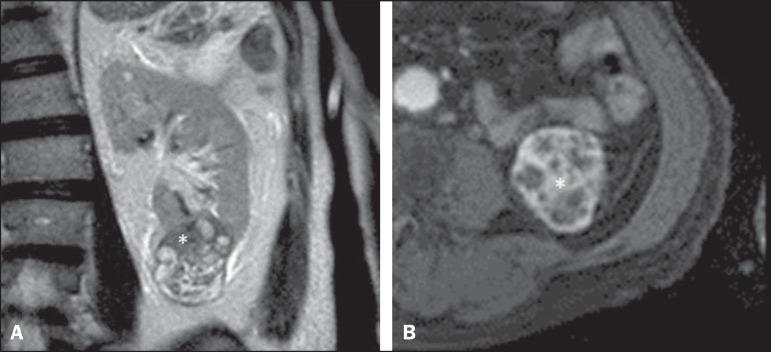

MATERIALS AND METHODS

Two independent radiologists retrospectively analyzed 46 consecutive patients with renal masses, between 2008 and 2012, using the R.E.N.A.L. nephrometry score (RENAL-NS), which is based on the evaluation of five anatomical features of the tumor, as evaluated with computed tomography or magnetic resonance imaging: adius, xophytic/endophytic properties, earness to the collecting system, nterior or posterior descriptor, and ocation relative to the polar line. Tumor complexity was graded as low, intermediate, or high. The interobserver agreement was calculated for the total score and for the score for each parameter. Surgical excision of the tumors was used as the standard of reference.

材料与方法

两名独立的放射科医生回顾性分析了2008年至2012年间连续的46例肾肿块患者,使用基于肿瘤五个解剖特征评估的R.E.N.A.L.肾计量评分(RENAL-NS),这些特征通过计算机断层扫描或磁共振成像进行评估:半径、外生/内生特性、与集合系统的接近程度、前后描述符以及相对于极线的位置。肿瘤复杂性分为低、中、高三个等级。计算观察者间在总分及各参数得分上的一致性。以肿瘤的手术切除作为参考标准。